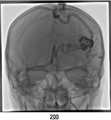

도 3a는 본 발명의 일실시예에 따라 획득된 조영제를 넣기 전의 제2영상의 예시도면이다.

FIG. 3A is an exemplary view of a second image obtained before incorporating the contrast agent obtained according to an embodiment of the present invention. FIG.

고해상도 영상인 제1영상(100)과 저해상도 영상인 제2영상(200)을 획득한다(S100). 고해상도 영상(제1영상(100))은, 도 2에서와 같이, 많은 픽셀로 구성되어 공간적으로 선명하여 혈관 내 위치를 정확한 파악이 용이한 영상을 의미한다. 저해상도 영상(제2영상(200))은, 도 3에서와 같이, 고해상도 영상에 비해 비교적 해상도가 낮아(즉, 각 프레임당 영상을 구성하는 픽셀의 수가 적어) 선명도가 떨어지는 영상을 의미한다. 컴퓨터는 영상촬영장비에 제1영상(100) 및 제2영상(200) 촬영을 직접 요청하여 획득할 수 있고, 영상촬영장비에 의해 이미 촬영된 제1 및 제2영상(200)을 컴퓨터 내부 또는 외부서버에 저장해두고 분석을 수행할 때 불러올 수 있다.The

예를 들어, 상기 영상이 조영제를 주사하여 촬영한 혈류영상(즉, 혈관조영영상)인 경우, 시계열데이터는 특정시간 간격으로 획득된 제2영상(200) 프레임을 통해 측정된, 각 지점의 시간별 조영제에 의해 증강된 신호의 측정량 데이터일 수 있다. 혈관조영영상은 각 프레임마다 조영제에 의해 특정 영역이 증강된 2차원 영상을 포함하고 있다. 즉, 조영제를 주사하기 전에는, 도 3a에서와 같이, 조영 증강된 혈관영역이 존재하지 않다가, 동맥으로 조영제가 주사되면, 도 3b에서와 같이, 동맥영역이 밝아졌다가 시간이 흐름에 따라 조영제가 혈류와 함께 정맥쪽으로 이동하면서, 도 3c에서와 같이 정맥영역이 밝아지게 된다. 컴퓨터는 각 프레임 내에서 사용자가 선택한 특정한 지점(즉, 특정한 좌표)에 대응하는 밝기값을 추출한다. 상기 컴퓨터는 상기 추출된 밝기값을 각 프레임이 획득된 시간 순서에 따라 시계열데이터로 생성할 수 있다. 예를 들어, 혈관조영영상의 총 프레임 수가 n개인 경우, 1*N의 행렬을 생성하여 추출한 밝기 값을 순서대로 상기 행렬 내에 입력할 수 있다. 상기 컴퓨터는 상기 행렬 데이터를 바탕으로 그래프를 생성(plot)하는 등의 시계열 분석을 수행할 수 있다.For example, when the image is a blood flow image (i.e., an angiogram image) taken by scanning the contrast agent, the time series data may include time-series data measured through a